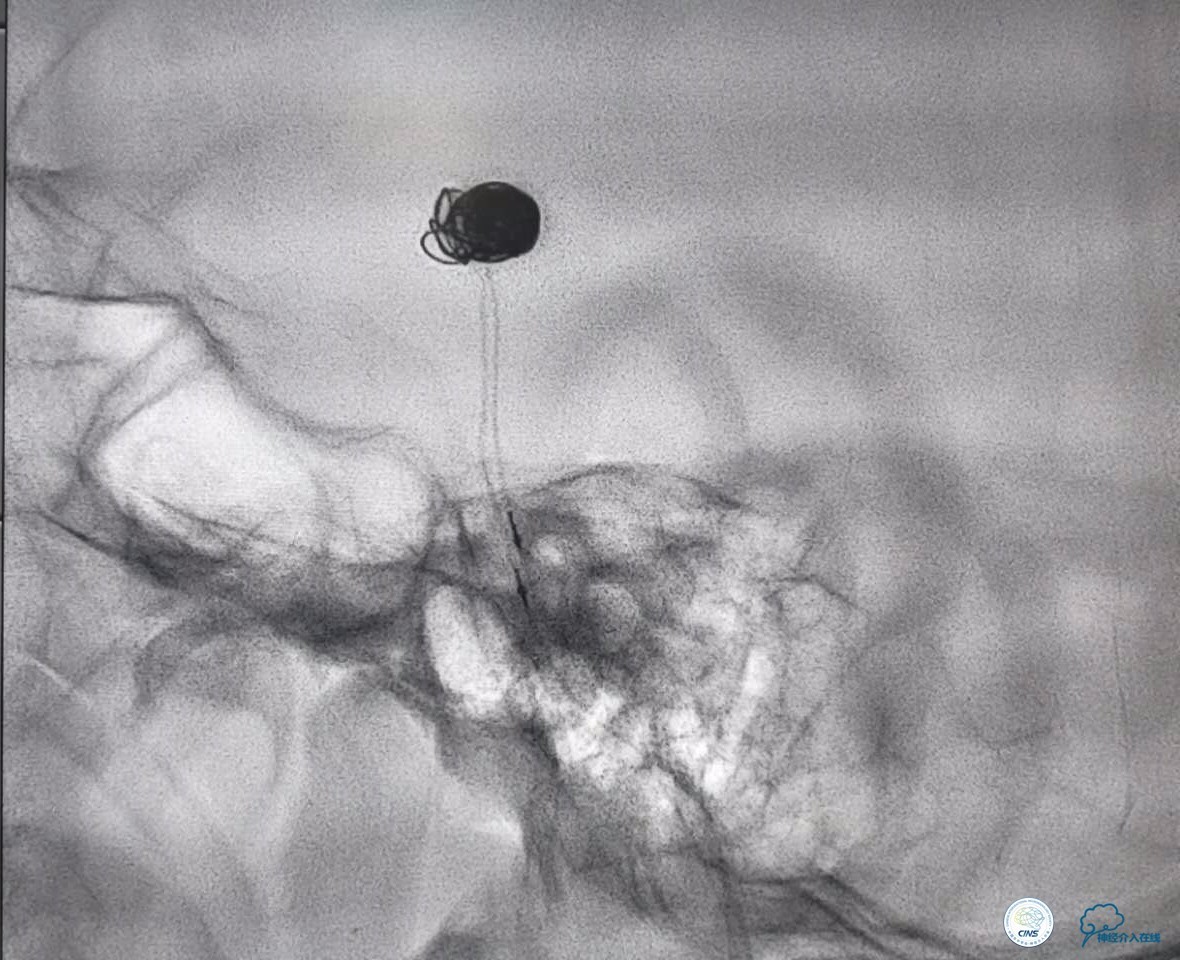

分别选择了7mmx30cm、6mmx30cm、2个4mmx15cm、3mmx8cm、2mmx8mm Target共6个弹簧圈进行栓塞。

术后

术后患者神志清楚,术后肢体运动较术前未见明显异常。

前两个弹簧圈对动脉瘤的瘤颈和动脉瘤的后部进行了栓塞。成篮稳定以后,开始对动脉瘤的内部和前部进行栓塞。

这个手术的难点是在保证动脉瘤致密栓塞的同时,要保证双侧大脑后动脉的通畅。最终手术达到了较好的效果。

术后患者神志清楚,术后肢体运动较术前未见明显异常。双微管技术降低了患者治疗的费用。同时避免了支架置入以后,终生服用抗血小板药物的情况。